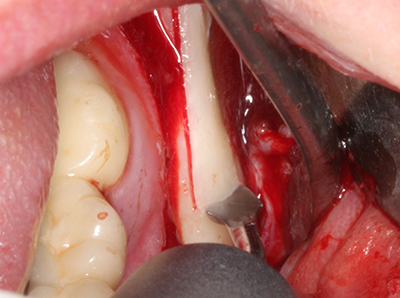

Indication: Bone splitting

Bone tissue is not simply a mineral structure but also contains a substantial proportion of collagen fibres. This means it not only has good compressive strength but also a degree of flexibility, which can be taken advantage of when performing bone augmentations. In the classical expansion procedure using bone splitting, the atrophied alveolar ridge is split longitudinally and carefully expanded after reaching an adequate osteotomy depth (Fig. 13-16), ideally without substantial removal of the periosteum (Brugnami, Caiazzo et al. 2014, Stricker, Fleiner et al. 2014). Screw and plate systems with increasing expansion distance have proven effective in separating the two bone lamellae while remaining below the fracture threshold. In general, residual bone widths of at least 3–4 mm are required (Chiapasco, Zaniboni et al. 2006) to guarantee adequate flexibility and sufficient bone coverage of the future implants. If necessary, a vertical relief osteotomy on one or both sides can improve flexibility. A combination with additional augmentation techniques, particularly on the buccal side, has been described as an alternative to the classical technique.

The splitting procedure is particularly atraumatic and there is no significant loss of dimension when using piezosaws, and there are no significant differences between implants in split jaws and implants in an alveolar ridge without a bone deficit (Chiapasco, Zaniboni et al. 2006, Danza, Guidi et al. 2009). However, sufficient continuous irrigation is essential, particularly with locally restricted and deep splitting to prevent thermal stress in the apical osteotomy regions.